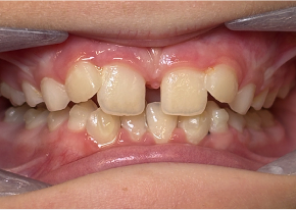

10 years 0 months old, 18 stages of Invisalign Palatal Expanders

Courtesy of Dr. Sandra Khong Tai

Pre Invisalign Palatal Expander Expansion

Post Invisalign Palatal Expander Expansion

After Invisalign First treatment